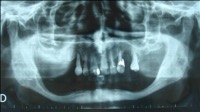

Il faut rechercher également les foyers infectieux et préciser la situation des sinus maxillaire et du nerf mandibulaire (qui traverse la mandibule) avant d’envisager la pose d’implants.

En cas d’obstacle anatomique (nerf trop proche, quantité d’os insuffisante…) une chirurgie pré-implantaire doit être programmée. Ainsi des greffes osseuses peuvent être envisagées avant la pose des implants, ou un déroutement des nerfs dentaires.